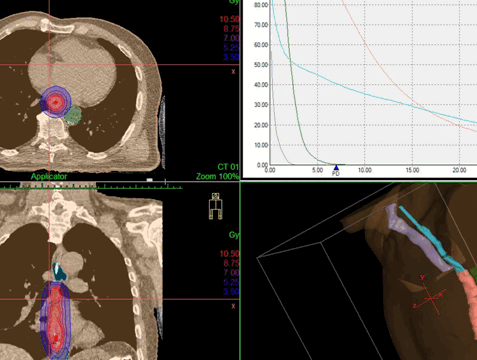

Дозное распределение, получаемое при дистанционной конформной лучевой терапии и внутрипросветной брахитерапии